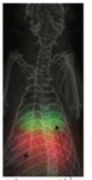

MPI磁粒子小动物活体成像性能优势 1. 易转化到人,用临床SPIO示踪剂。 2. Nm级灵敏度,可检测个位数细胞。 3. Mm级分辨率,目前达到0.3mm。 4. 信号不随深度衰减,3D断层扫描。 5. 可以长达数个月的连续示踪成像。 6. SPIO无毒无放射,代谢成血红素。 7.定量分析。 主要应用 多模态成像;活体成像;干细胞及各种类细胞示踪;肿瘤检测示踪(肿瘤微环境/肿瘤免疫微环境);免疫炎症示踪;心脑血管成像;血管灌注成像;准确靶向磁热疗;准确靶向药物输送;肿瘤免疫治疗(局部免疫刺激);纳米粒子开发。 肿瘤免疫治疗是全球趋势 临床应用前景 1.得到美国NIH的资金支持,正在合作研发可用于临床的MPI. 2. 区别于CT、MRI、和PET等,MPI成像没有任何辐射,不需要使用任何有毒性的示踪剂。使用临床许可的超顺磁性氧化铁纳米颗粒(SPIO):安全性通过临床审查,特别是可用于肾功能不全或肾脏损伤的病人。 3. SPIO这种纳米尺寸的氧化铁粒子在体内可以分解并转化为血红素,完全的支持长期诊断检测,无任何累计辐射或毒性。 |